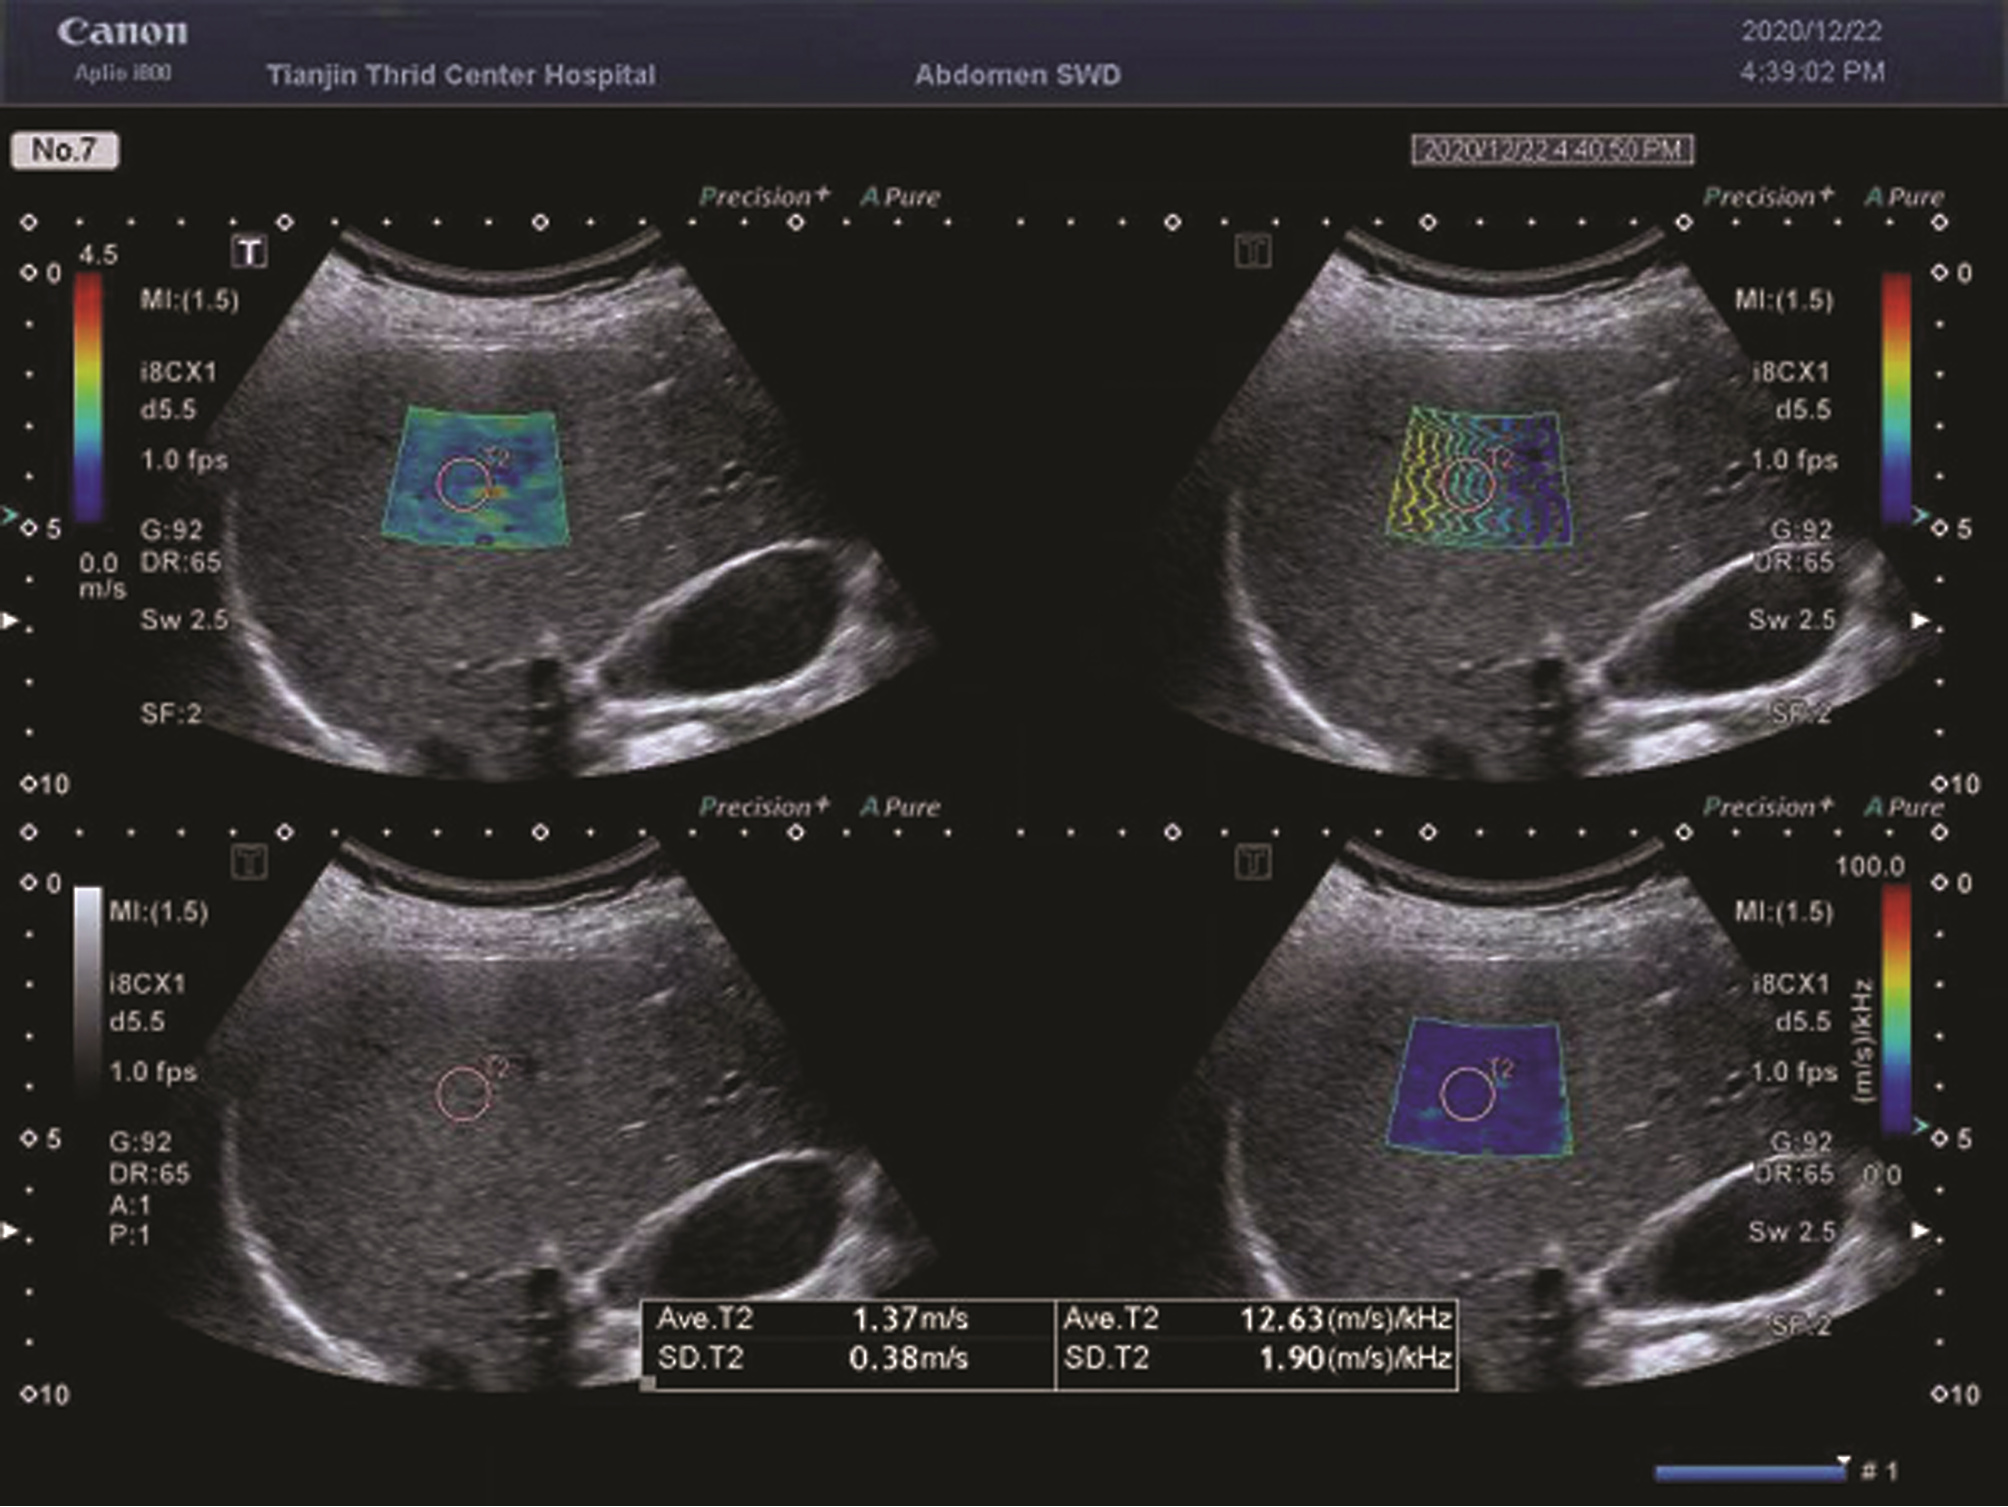

•   Objective  To investigate the clinical value of Canon two-dimensional ultrasound shear wave elastography (SWE) and shear wave dispersion (SWD) in the diagnosis of high-risk esophageal and gastric varices in compensated cirrhosis.  Methods  A total of 58 patients with compensated cirrhosis of various etiologies who received electronic gastroscopy in Tianjin Third Central Hospital from February 2020 to February 2021, and Canon Aplio i800 color ultrasound instrument was used to perform SWE and SWD of the liver. According to the results of gastroscopy, the patients were divided into high-risk esophageal and gastric varices group (HREGV group) with 22 patients and non-high-risk esophageal and gastric varices group (NHREGV group) with 36 patients. The independent samples t-test was used for comparison of normally distributed continuous data between two groups, and the non-parametric Mann-Whitney U test was used for comparison of non-normally distributed continuous data between two groups; the chi-square test was used for comparison of categorical data between two groups. A multivariate logistic regression analysis was used to analyze and screen out the noninvasive indicators for predicting high-risk esophageal and gastric varices, and the receiver operating characteristic (ROC) curve was used to evaluate the clinical value of liver SWD and SWE in the diagnosis of high-risk esophageal and gastric varices.  Results  There were significant differences between the HREGV group and the NHREGV group in SWD (t=-3.84, P < 0.001), etiology (χ2=9.67, P=0.022), total bilirubin (Z=-2.00, P=0.045), spleen diameter (t=-2.44, P=0.018), and portal vein diameter (Z=-1.96, P=0.005). The patients with compensated cirrhosis had a mean liver SWD of 15.17±2.45 m·s-1·kHz-1, and the HREGV group had a significantly higher liver SWD than the NHREGV group (16.59±2.66 m·s-1·kHz-1 vs 14.31±1.86 m·s-1·kHz-1, t=-3.84, P < 0.001), while there was no significant difference in SWE between the two groups (Z=-1.21, P=0.223). SWD was an independent risk factor for high-risk esophageal and gastric varices in patients with compensated liver cirrhosis (odds ratio=1.67, 95% confidence interval: 1.17-2.39, P=0.005). In the diagnosis of high-risk esophageal and gastric varices, SWD had an area under the ROC curve (AUC) of 0.786, with a specificity of 80.56% and a sensitivity of 81.82% at the optimal cut-off value of 15.35 m·s-1·kHz-1; SWE had an AUC of 0.596, with a specificity of 52.78% and a sensitivity of 68.18% at the optimal cut-off value of 9.25 kPa.  Conclusion  Liver SWD measured by Canon Aplio i800 color ultrasound is excepted to become a new noninvasive method to predict the presence of high-risk esophageal and gastric varices in patients with compensated cirrhosis, while SWE has a limited diagnostic value.